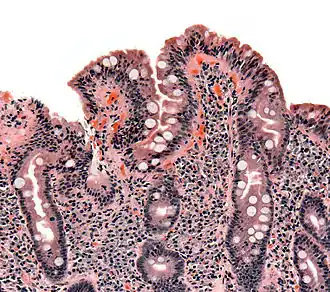

Biopsie duodénale

Si la sérologie est positive, une endoscopie de l'intestin grêle avec biopsies sera pratiquée. La fibroscopie peut montrer des anomalies non spécifiques : aspect en mosaïque, plis raréfiés de la muqueuse[56]…

Même en cas de normalité de l'aspect, une confirmation doit être faite par biopsie de la muqueuse duodénale. Elle doit être multiple (4 à 6 échantillons[43]) en raison d'une atteinte pouvant être partielle.

Elle met en évidence une atrophie villositaire associée à une augmentation des lymphocytes intraépithéliaux, une hypertrophie des cryptes et une infiltration plasmolymphocytaire du chorion. Ces lésions sont évaluées selon la classification de Marsh, allant de I (simple augmentation isolée des lymphocytes intraépithéliaux) à IIIc (atrophie villositaire sévère)[53].

Chez l'enfant, si la sérologie ne fait pas équivoque, l'endoscopie peut être évitée[57].